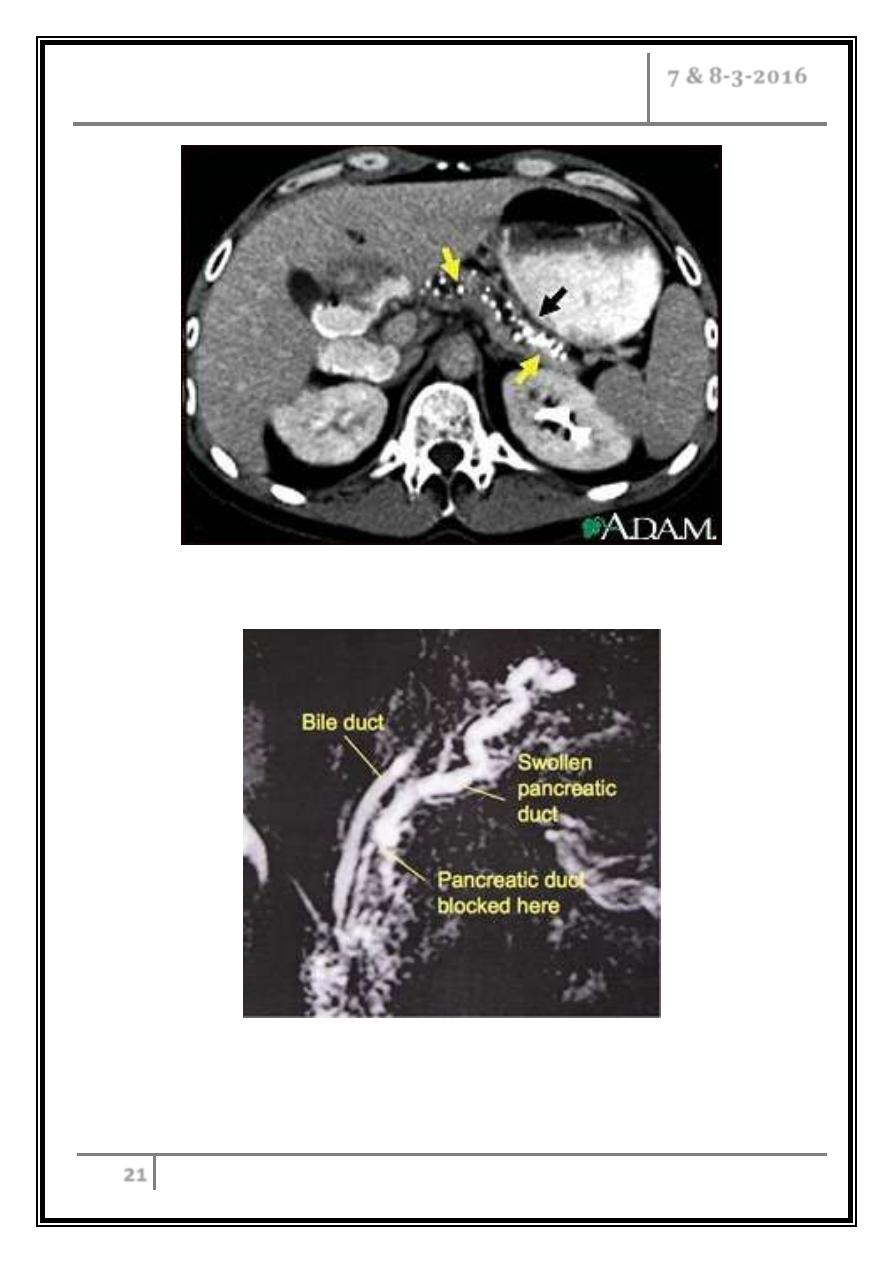

CT scan of the upper abdomen showing multiple white-colored

calcifications. These occur in chronic pancreatitis

This MRCP picture shows chronic pancreatitis causing a narrowing of

the pancreatic duct, with a swollen tortuous duct visible upstream